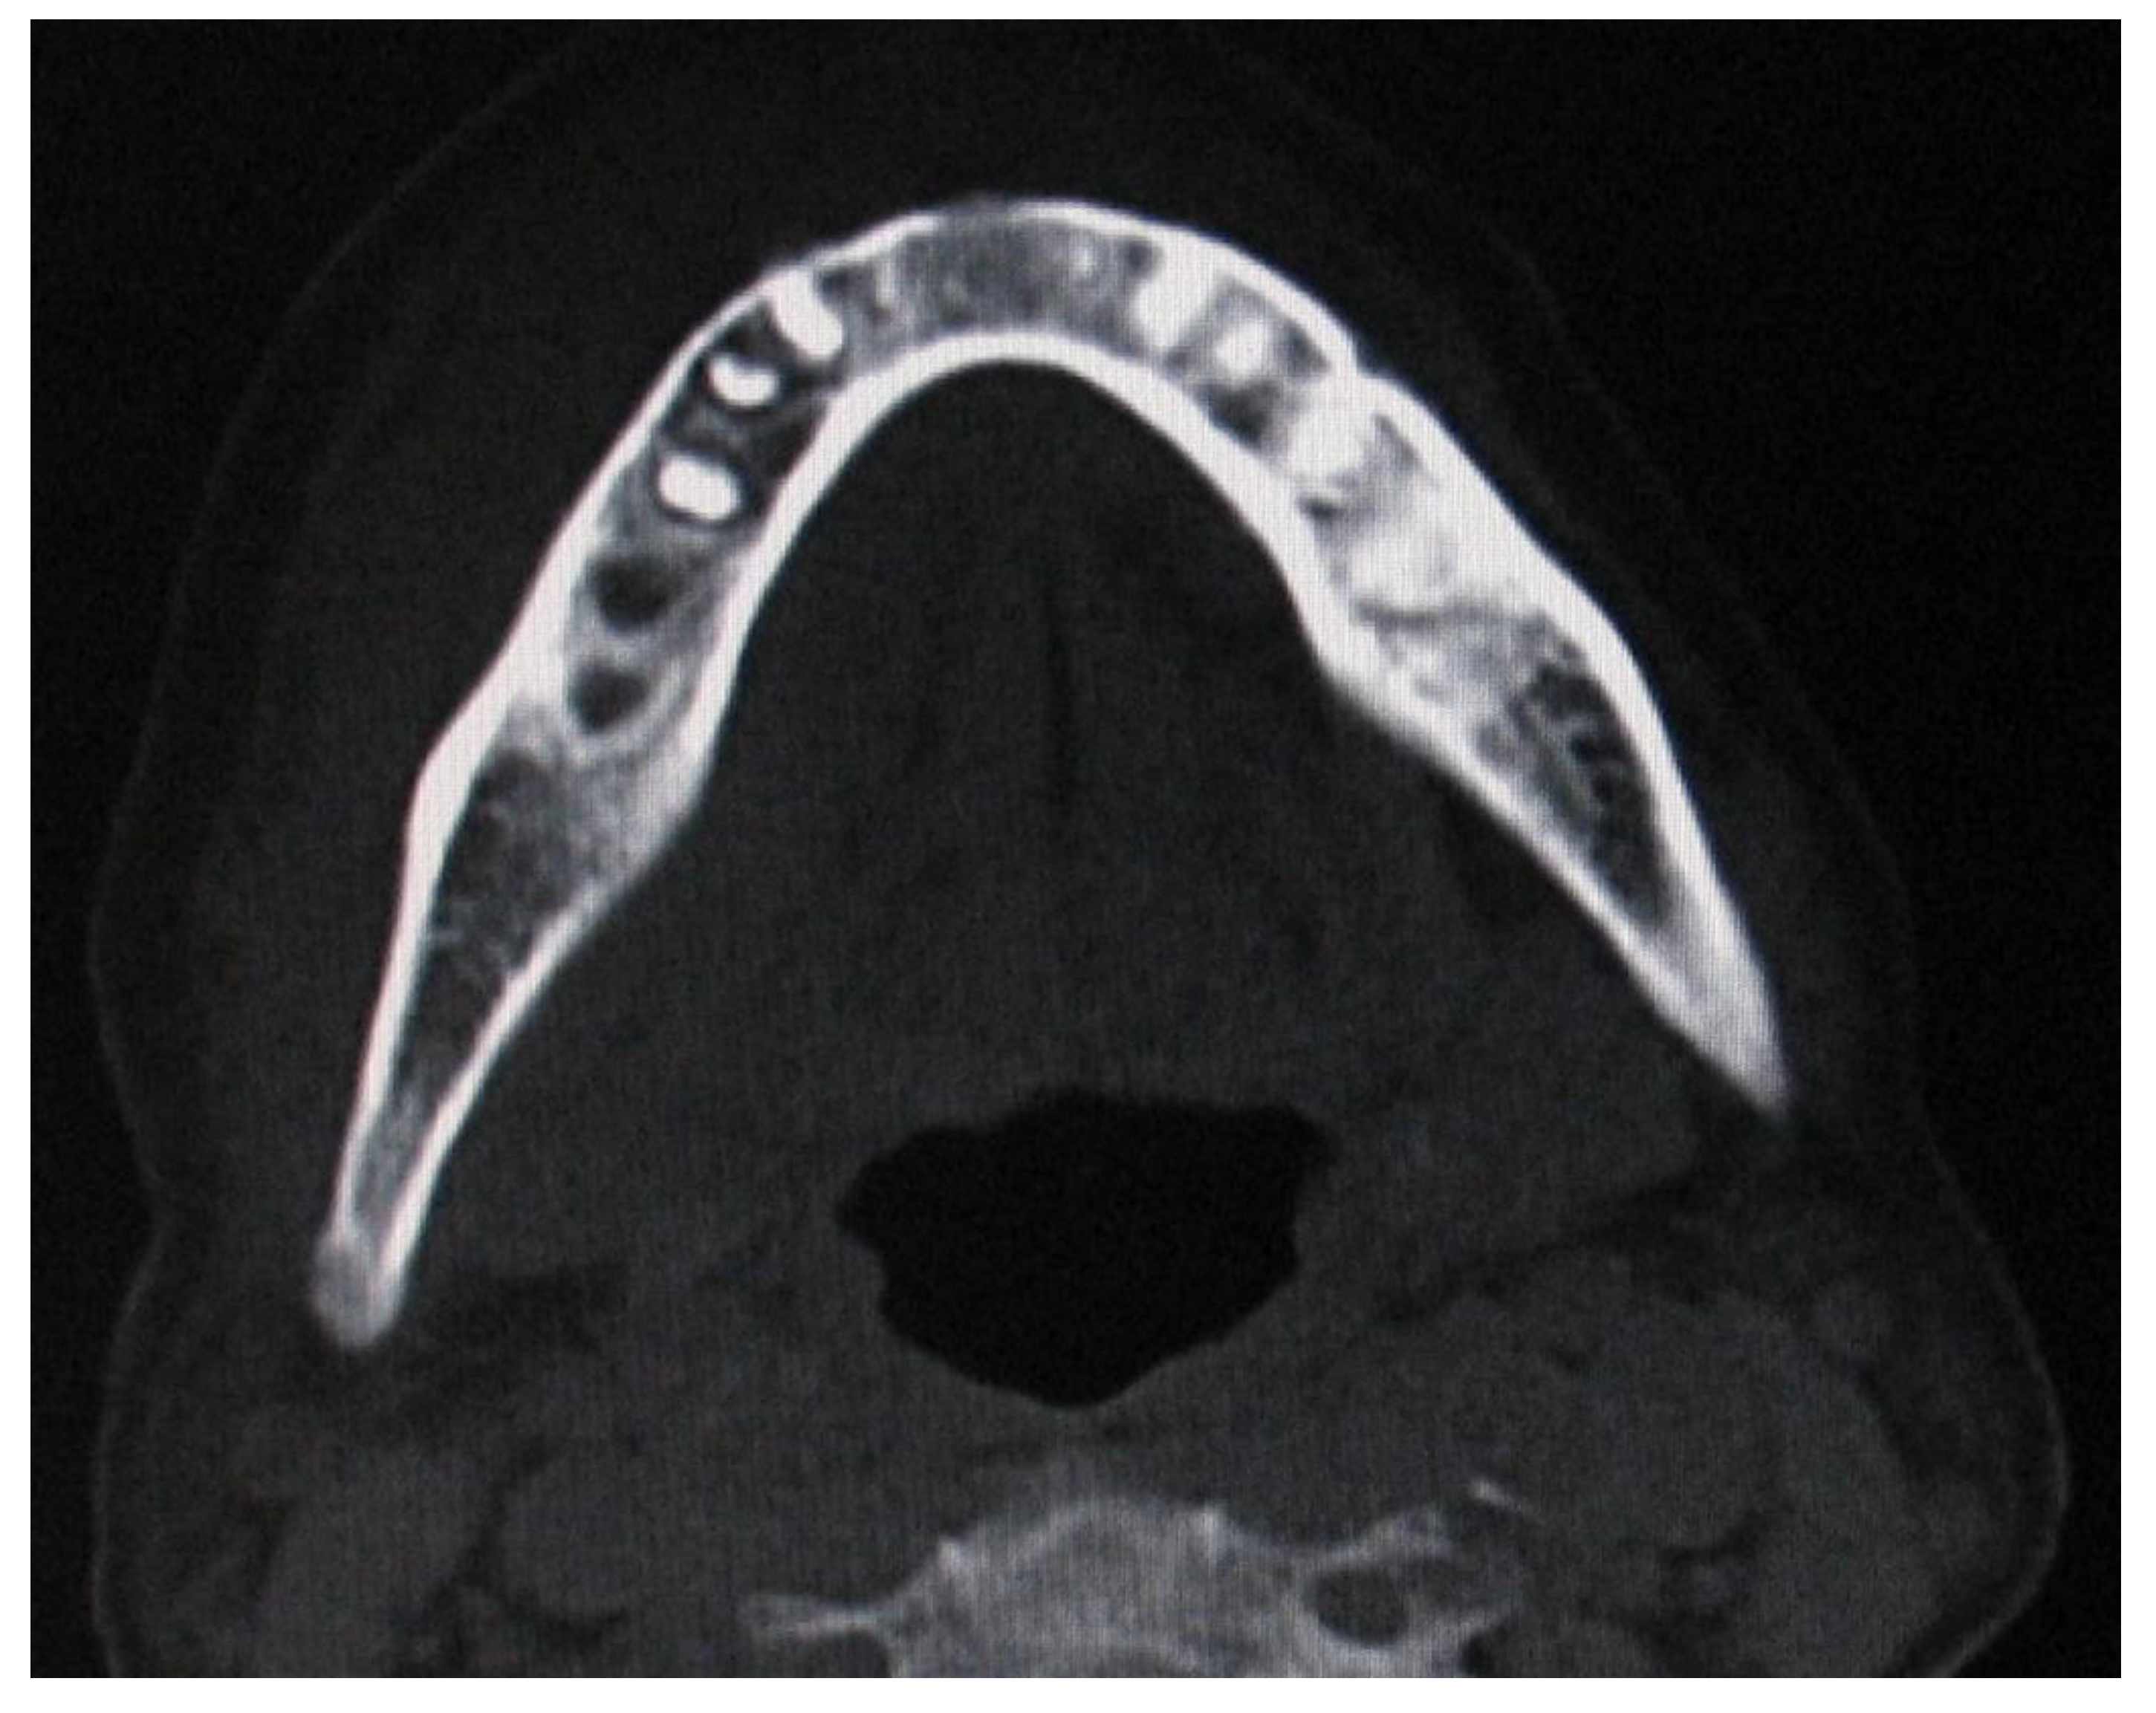

| 20 | 2018 | F | 60 | N/A | Mandible | Swelling, pain, tooth mobility, paresthesia | 5 | DLBCL | - | CT/died |